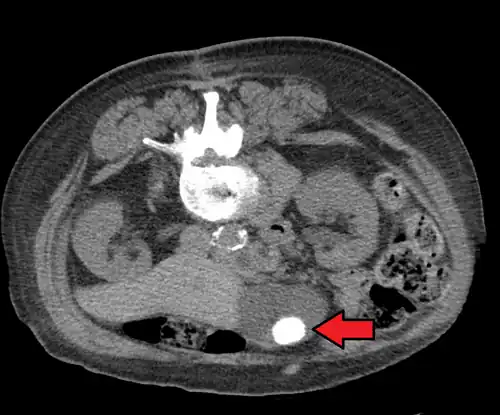

Diagnosis is typically confirmed by abdominal ultrasound. Other imaging techniques used are ERCP and MRCP. Gallstone complications may be detected on blood tests.[2]

On abdominal ultrasound, sinking gallstones usually have posterior acoustic shadowing. In floating gallstones, reverberation echoes (or comet-tail artifact) is seen instead in a clinical condition called adenomyomatosis. Another sign is wall-echo-shadow (WES) triad (or double-arc shadow) which is also characteristic of gallstones.[43]

Large gallstone as seen on CT

Large gallstone as seen on CT -